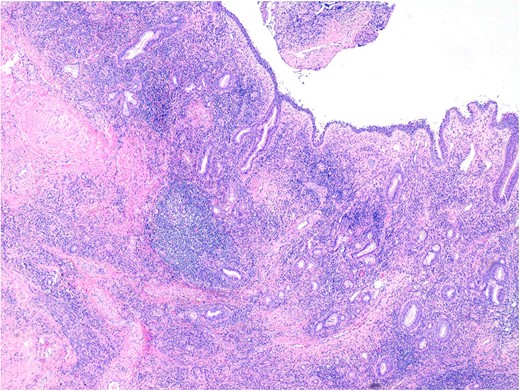

Histopathology demonstrated stromal storiform and perivascular concentric fibrosis with a prominent chronic inflammatory infiltrate (Fig. 2). This consisted of mature lymphocytes, mature plasma cells and eosinophils (Fig. 3). Arteritis (a feature of GPA) was not seen. On digital microscopy, the IgG4 plasma cell counts were 98–120/HPF and IgG4:IgG ratios of 0.4–0.7.

Sinonasal mucosa showing marked chronic inflammation and stromal fibrosis. 40× magnification. H&E.